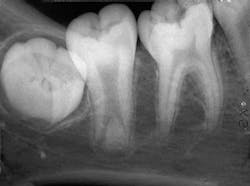

Based on the clinical examination of the patient, selected periapical radiographs, bitewings, and a panoramic film were ordered and exposed. A review of the periapical films revealed a mandibular second molar with an elongated pulp chamber and an abnormally low furcation region (see radiograph). Clinically, the second molar appeared normal in size and shape. No other abnormalities were noted on the radiograph.

Radiographic features

A taurodont is recognized by its characteristic radiographic appearance. The overall tooth length is normal, but the distance from the cementoenamel junction to the furcation is increased. The pulp chamber is greatly enlarged without a constriction at the cementoenamel junction. The rectangular shape of the pulp chamber resembles that of cud-chewing animals. The roots appear to extend only a short distance from the furcation and exhibit short root canals. Radiographically, the taurodont tends to have an overall "stretched" appearance.